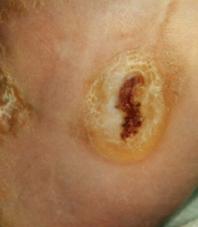

Perforating ulcer of the left foot, plantar 12 x 14 mm with a depth of 5 mm.

For wound therapy application of a sterile LIGASANO® white pack, soaked with Ringer´s solution. For stabilisation and pressure distribution supply with a cast adapted to neuropathy. Wound closure under therapy with LIGASANO® white within 36 days resp. 4 month.